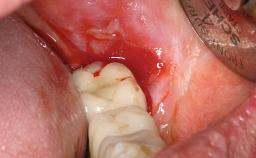

Peripheral Giant-cell Granuloma Associated with Peri-implant Tissues

Soft Tissue Contour and Volume Slightly compromised